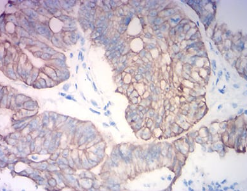

KRT19 Mouse Monoclonal antibody[7B8C1]

The protein encoded by this gene is a member of the keratin family. The keratins are intermediate filament proteins responsible for the structural integrity of epithelial cells and are subdivided into cytokeratins and hair keratins. The type I cytokeratins consist of acidic proteins which are arranged in pairs of heterotypic keratin chains. Unlike its related family members, this smallest known acidic cytokeratin is not paired with a basic cytokeratin in epithelial cells. It is specifically expressed in the periderm, the transiently superficial layer that envelopes the developing epidermis. The type I cytokeratins are clustered in a region of chromosome 17q12-q21. [provided by RefSeq, Jul 2008]

Species Reactivity:    Human, Rat